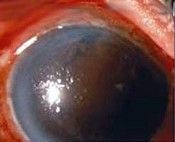

(如图)女性,患者,于15年行右眼囊外人工晶状体摘除术,在前房植入硬性人工晶状体片。现在右眼视力渐进性下降,该图为裂隙灯检查提示右眼角膜水肿及后弹力层炎症。下列说法正确的是()

-